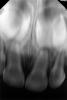

Видны корни верхних центральных и боковых молочных резцов.

В области верхушек корней нет больших выраженных «тёмных пятен» (очагов разрушения кости), как это бывает при обширном гнойном воспалении.

Но границы тканей у верхушек корней выглядят не очень чёткими, особенно у центральных резцов — это может быть признаком начального воспаления или изменений после травмы.

Также нужно помнить: на прицельных снимках у детей воспаление может быть не так явно выражено, как у взрослых, и оценка часто требует сравнения с клиническими симптомами (боль, подвижность, цвет зуба, десна).

👉 То есть: на вашем снимке нет яркой картины сильного воспаления, но врач мог заметить первые признаки изменений у верхушек и совместить их с клинической картиной (потемнение зуба → признак погибшего нерва).

На рентгенограмме (судя по проекции — это прицельный снимок переднего отдела верхней челюсти) видно:

На переднем плане хорошо просматриваются корни верхних центральных и боковых резцов (4 зуба).

Над ними — зачатки постоянных зубов, которые находятся в стадии формирования коронок. Это указывает, что снимок сделан у ребёнка (в период сменного прикуса).

Между корнями резцов заметна структура, похожая на расширенную носоподобную тень — это норма (носовая полость/резцовый канал).

Костная ткань вокруг зубов выглядит без признаков выраженного воспаления — нет явных участков разрежения.

Видна смена зубов — молочные резцы ещё на месте, а зачатки постоянных резцов находятся в стадии формирования и продвижения.

Патологий (кист, резорбции корней, деструкции кости) на этом снимке явно не прослеживается.